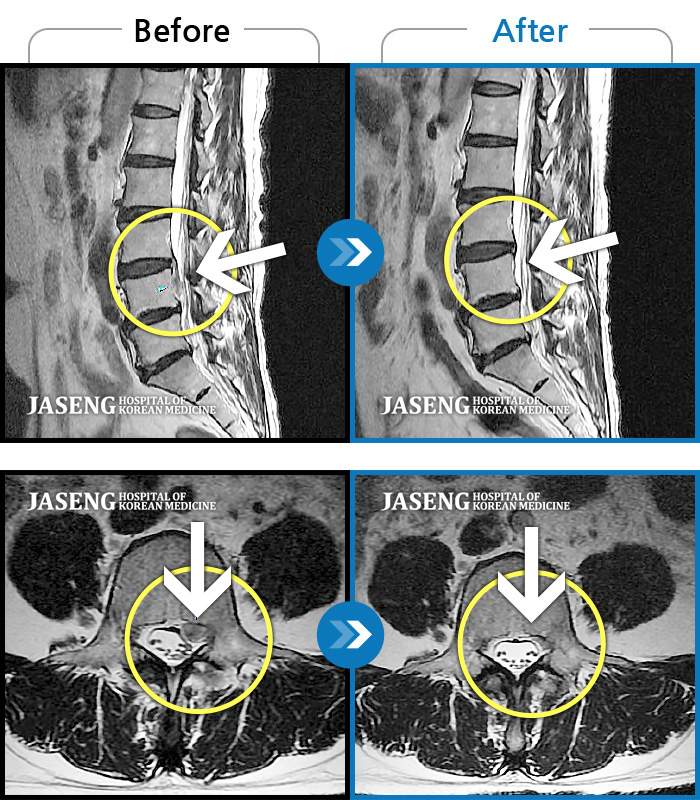

[뱸] 19.11.28~25.05.06